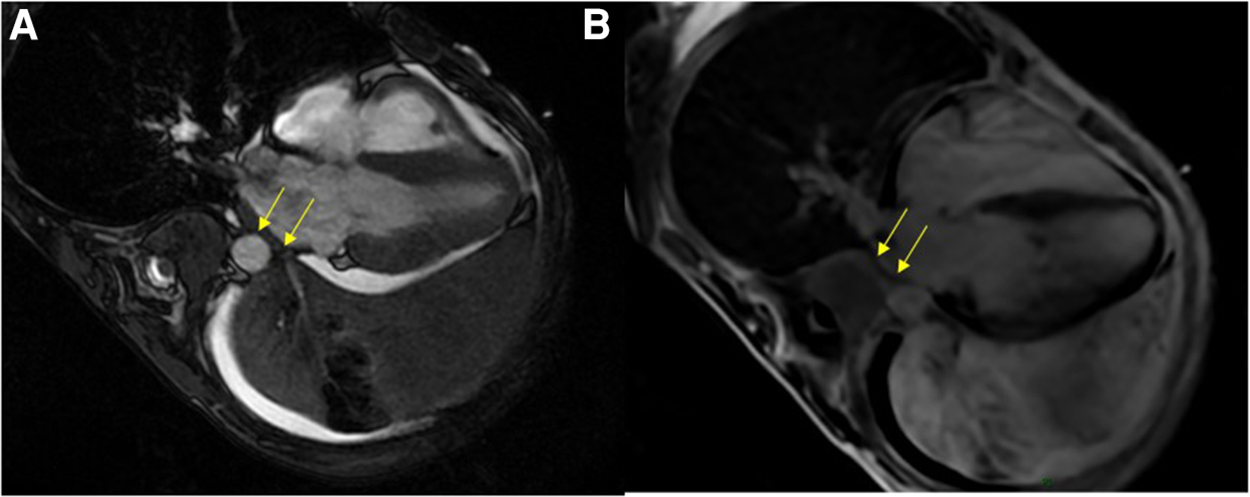

Etiological investigation was completed by performing cardiac MRI, which showed tumoral invasion into the pericardium and the lateral wall of the left atrium (Figure 2). Repeat TTE could not reproduce this finding.

Figure 2. Cardiac MRI. SSFP four-chambers view showing the extensive tumoral process in the left pulmonary area coming into close contact with the left atrium, with paraneoplastic pleural and pericardial effusions (A); and likely tumoral invasion of the left atrial wall on the late-gadolinium-enhanced acquisition (B). MRI, magnetic resonance imaging; SSFP, steady-state free precession.